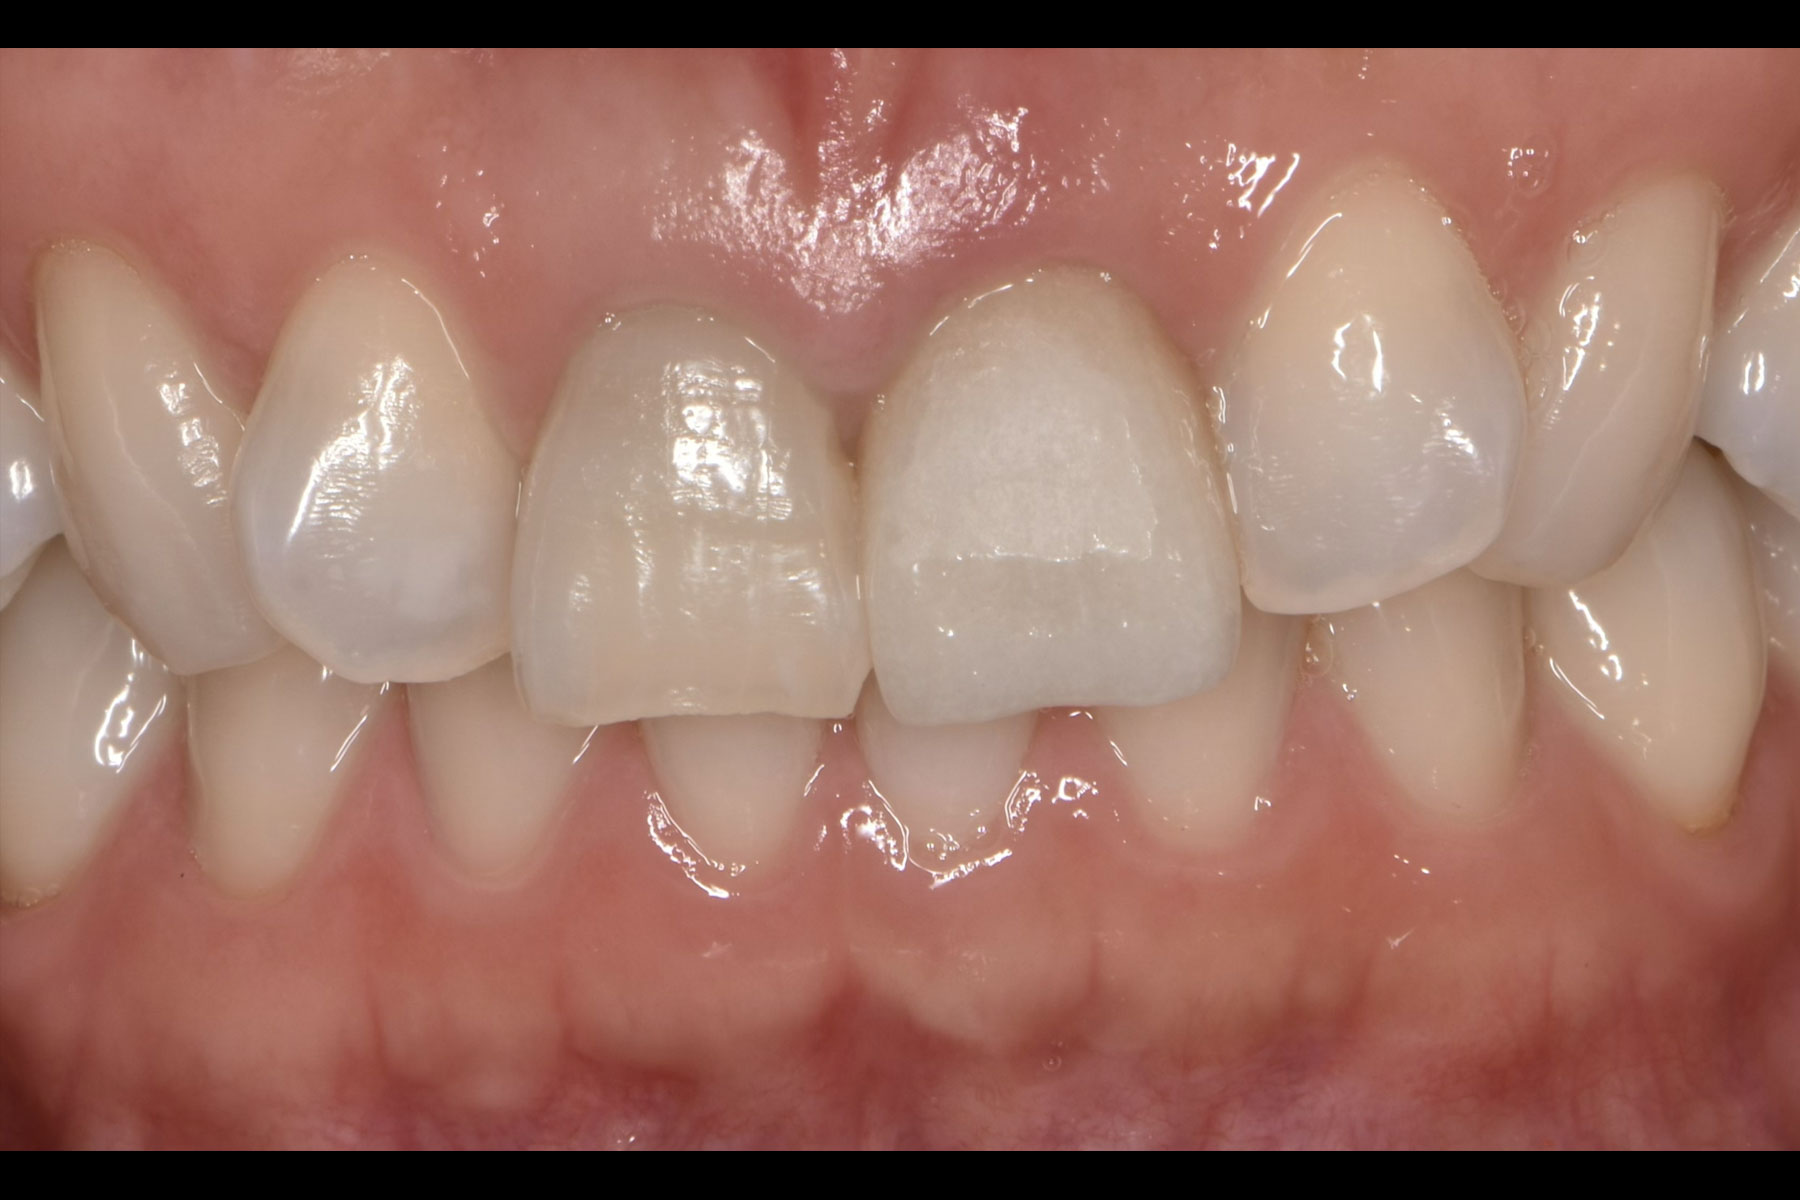

治療後